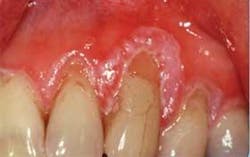

Oral examination: As you begin your intraoral exam, you notice that the gingival tissue is dark pink and appears ulcerated at the margins, especially around tooth Nos. 9–13 (see Figure 1). Rose tells you that this area is of concern to her and that this fact is really why she scheduled the appointment with you today. She is unhappy with the appearance of her teeth, and is worried about the bleeding that she has noticed during the past several months.

As you assess the tissue, you refer to the previous radiographs and digital slides from several years ago. You see a noticeable difference. The tissue today appears bulbous, spongy, ulcerative, and has much more recession than noted previously. As you probe the area, there is spontaneous bleeding. You report your findings to the dentist, and he requests a biopsy of the gingival tissue, referring her to an oral surgeon. Several days later, the pathology report indicates a diagnosis of squamous cell carcinoma of the gingiva.

Distinguishing characteristics: Figure 1 suggests a later stage squamous cell carcinoma of the gingiva. Squamous cell carcinoma of the gingiva may appear very benign in its early stages. It is only after the tissue begins to change appearance and rapidly grow that suspicion usually begins to take place. Intraoral digital photographs are especially important in comparing subtle tissue changes.